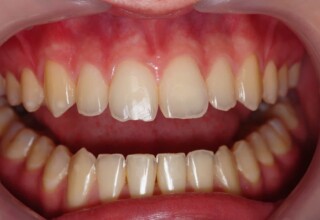

Whitening of non-vital teeth

Teeth with a root canal often lose their brightness and darken to an unesthetic level. Their bleaching requires an excellent root canal and patience. An adhesive filling is placed inside the root to confine the bleaching effect to the tooth part which is visible in the oral cavity. The actual bleaching may require 1-5 short sessions for the placement and renewal of the bleaching material. After the bleaching a high quality adhesive filling is mandatory.

Initial appearance

Final appearance